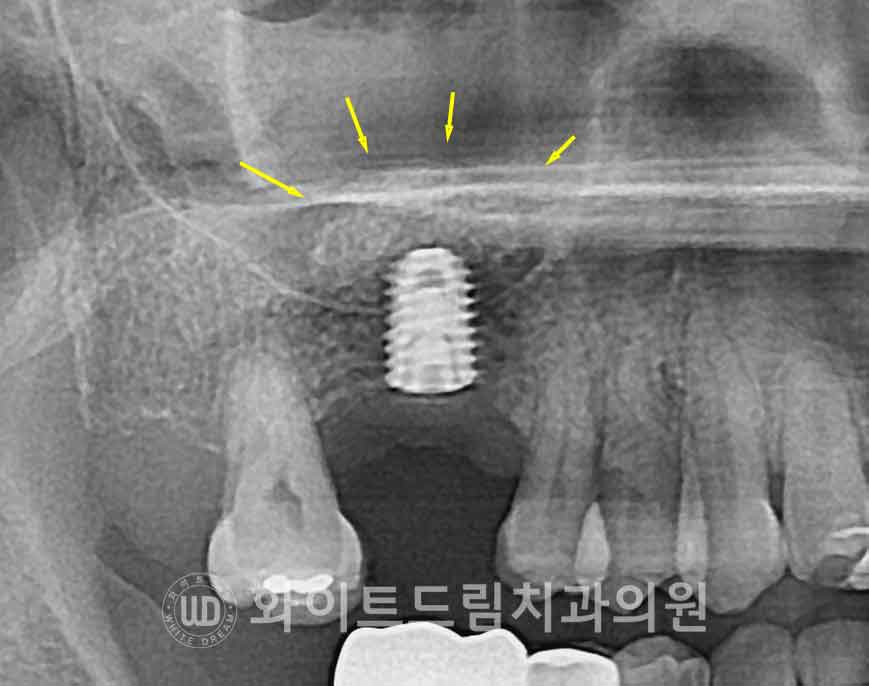

우선 엑스레이(X-ray) 상으로는,

이식된 골이 상악동저를 따라 매끄럽고 둥근 형태의

‘동산 모양’(dome shape)으로 형성되어 있는지를 확인합니다.

이 모양이 불규칙하거나 일부가 꺼져 있다면,

상악동막 손상 또는 이식재 흡수 가능성을 의심해 볼 수 있죠.

[동일 인물이며 동일 환경에서 촬영됨 / 강남역어금니임플란트 : 23.04.04 - 23.09.27]